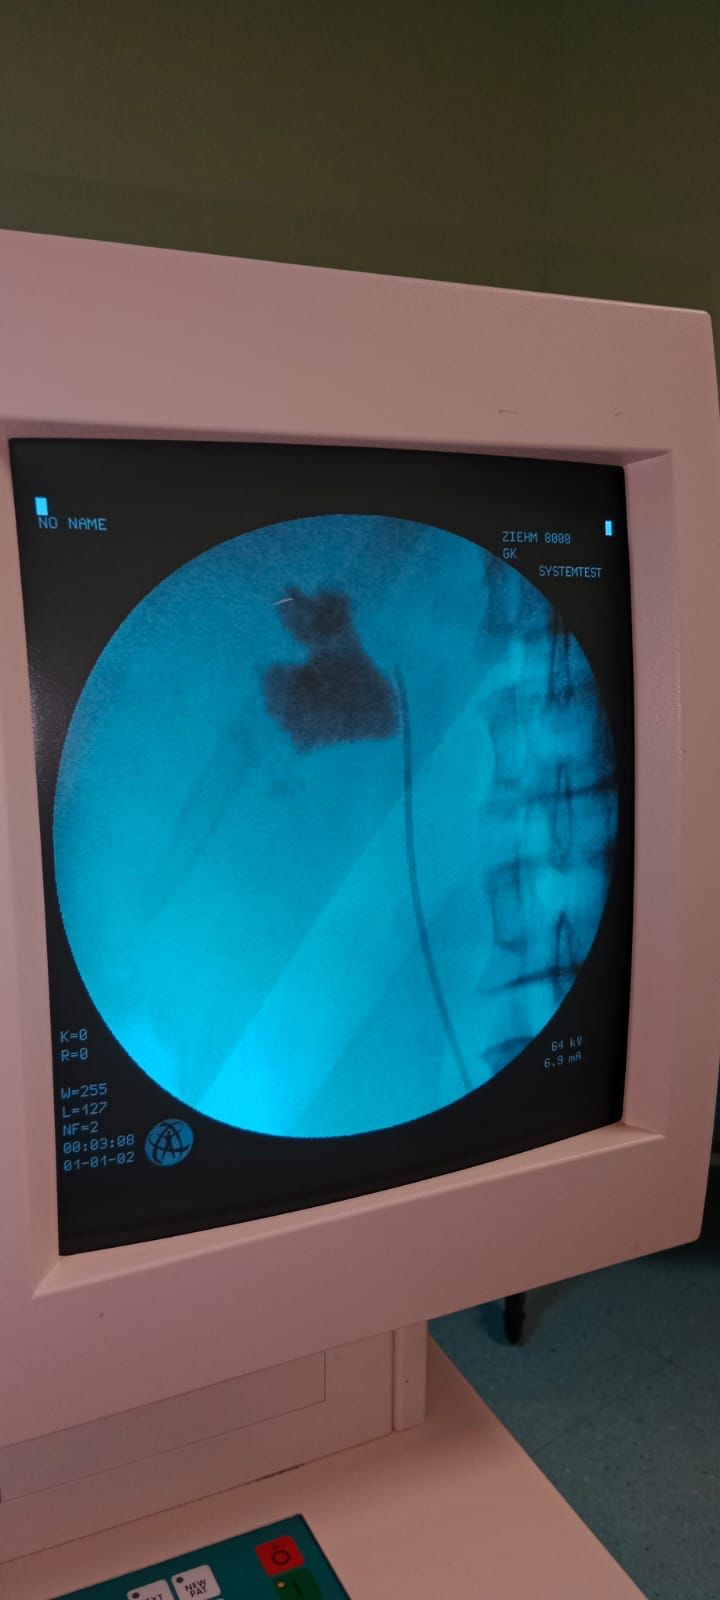

Kırşehir Eğitim ve Araştırma Hastanesi’ne başvuran İlhan Çakır’ın sol böbreğinde tespit edilen 6 santimetrelik taş, kapalı böbrek taşı ameliyatı (PNL) ile başarılı şekilde çıkarıldı. Üroloji Uzmanı Uzm. Dr. Talip Göktaş, operasyonun detaylarını paylaşarak yöntemin hastalara sağladığı avantajları vurgulayarak; “İlhan Çakır adlı hastamız Yozgat’tan sevkli geldi. Sol böbreğinde 5×6 cm’lik taşı mevcuttu. Kapalı böbrek taşı yöntemi PNL ile ameliyatı yapıldı. 1 gün sonra taburcu edildi. Bu yöntemle hastalarımız açık ameliyatlara göre erken dönemde işlerine dönebiliyor ve daha konforlu bir şekilde ameliyat sürecini atlatabiliyor.”